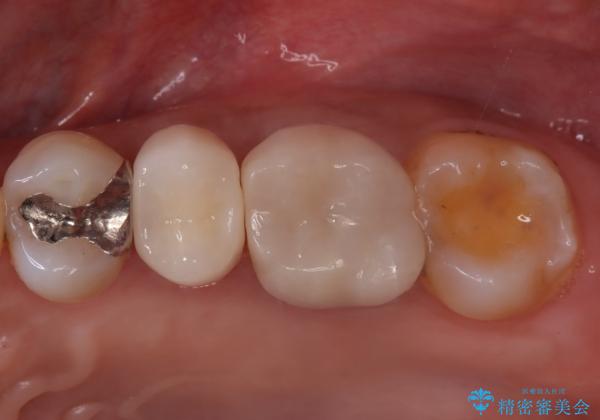

- 「何もしなくても歯が痛む、咬むと歯が痛む」を主訴に来院された患者さんです。検査の結果、歯髄の部分壊死と診断しました。根管治療を行いファイバーコアとオールセラミッククラウンで治療を行いました。

術前に神経の部分壊死と診断しましたが、神経をあけたときに出血が一切無かったので神経が死んでいるという診断は正しかったという事になります。

神経が死んでしまった原因はプラスチック(保険適用治療)の被せ物が劣化し歯と被せ物の間に生じた隙間からのリークが原因だと考えます。